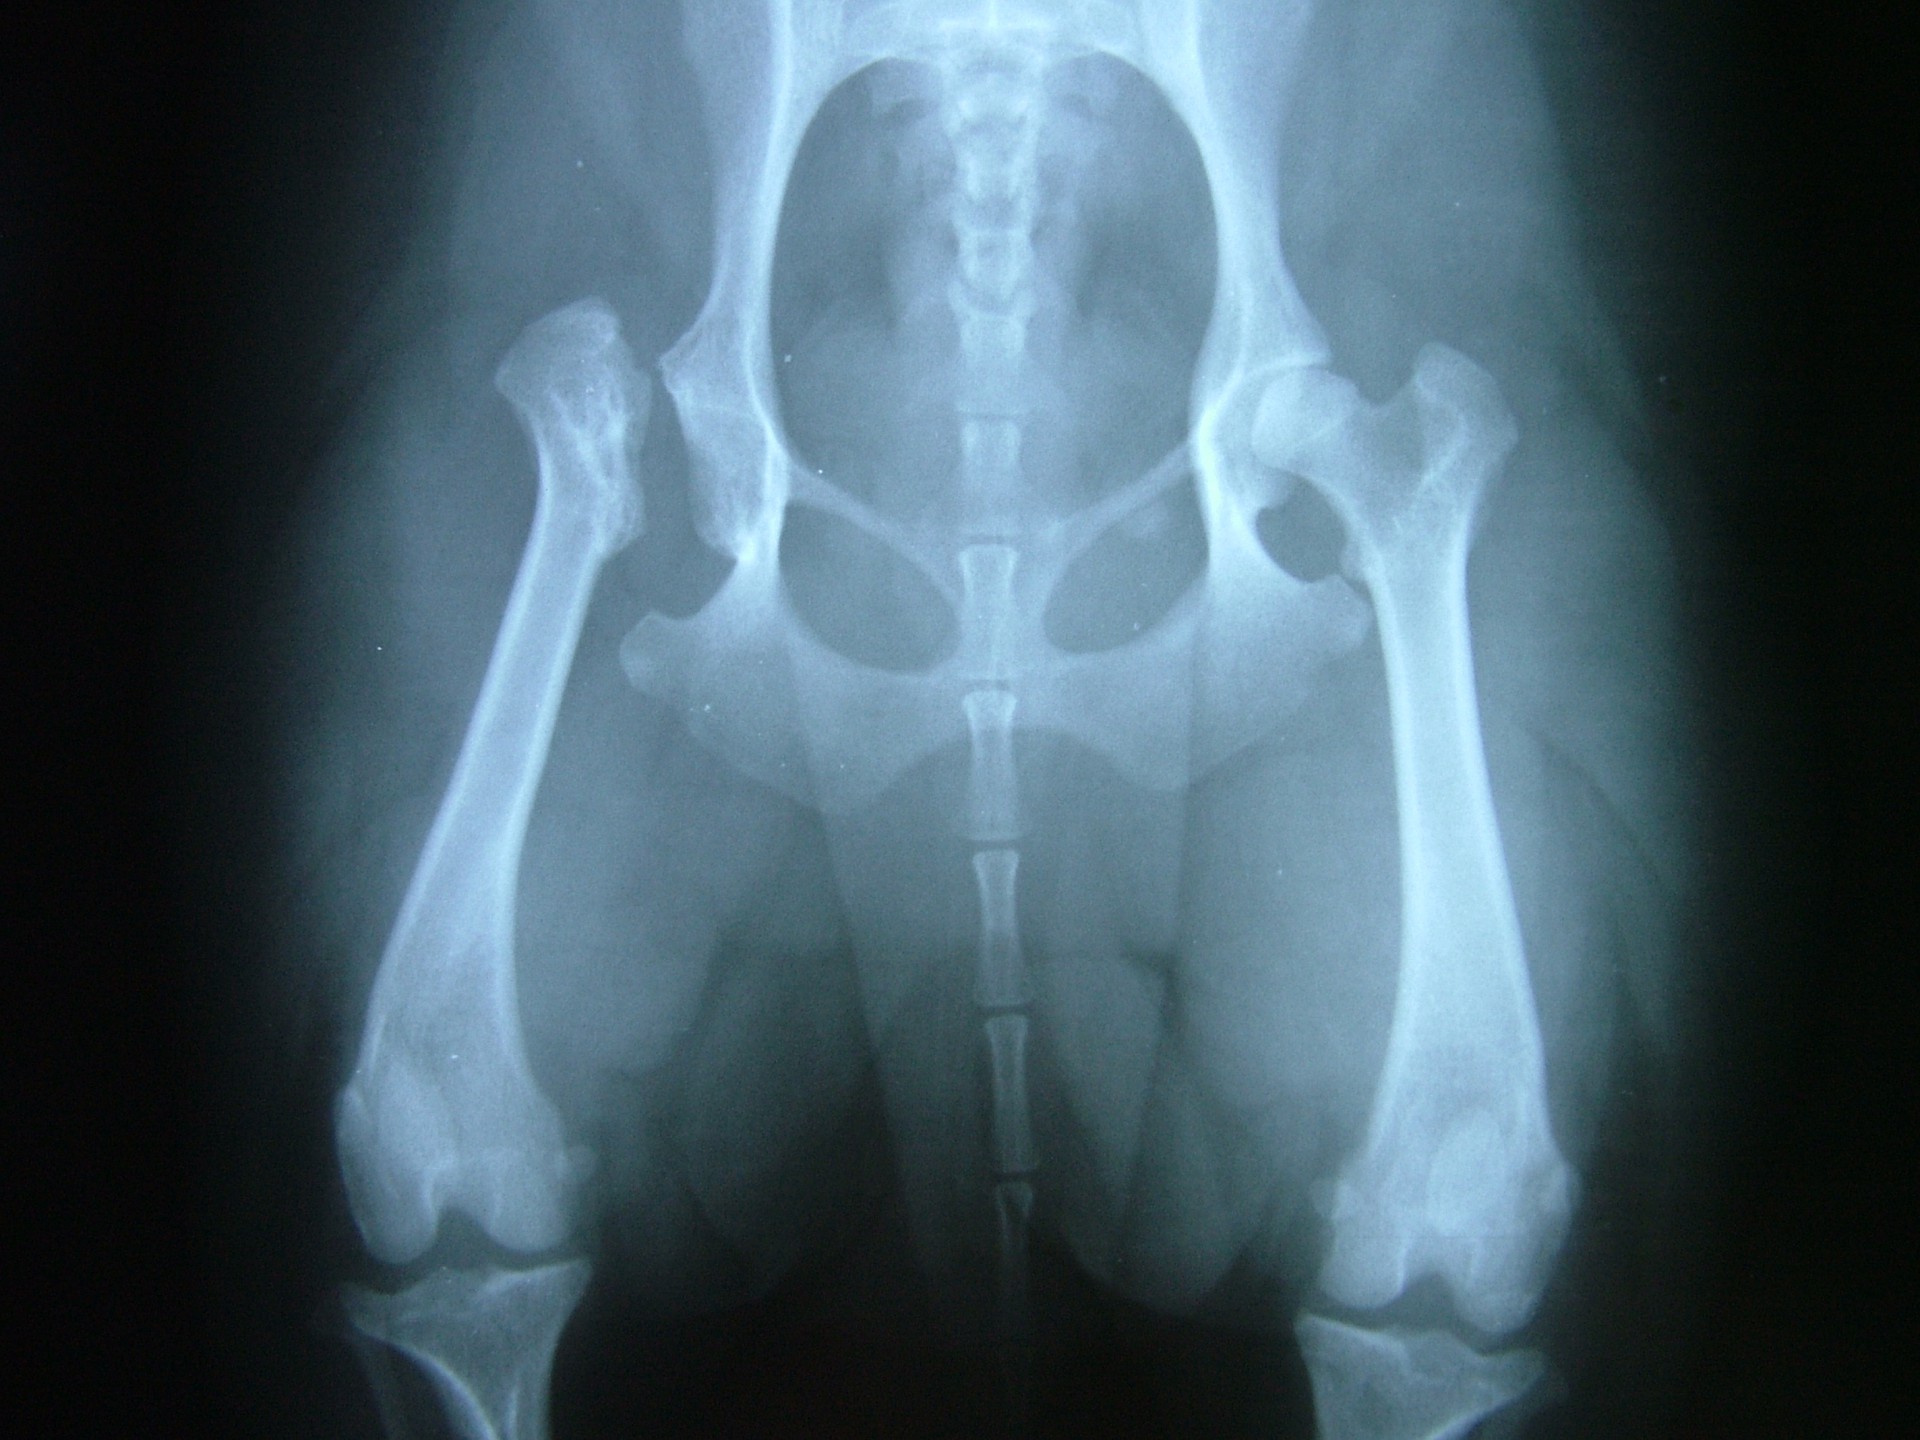

Az 1 év alatti kutyákban a hátsó lábon jelentkező enyhe fokú sántaság az első tünet, mellyel a tulajdonos általában az állatorvoshoz fordul. A csípőízület passzív mozgatására, rotálására az állat fájdalmat jelez. Az első tünetek megjelenésekor végzett klinikai vizsgálattal a csípőízületi fájdalom általában már a betegség gyanúját felkelti, ezért az ízület röntgen vizsgálatát is elvégezzük. Sok esetben azonban a klinikai tünetek megjelenése és a röntgen tünetek megjelenése nem esik egybe, ezért az enyhe fokú sántasággal járó korai szakaszban a betegség nem egyértelműen diagnosztizálható.

Ilyen esetben a 2-4 hét múlva elvégzett röntgen vizsgálat a Legg-Calve-Perthes kórt egyértelművé teszi.

A felvételen a combcsontfej csontos szerkezetének felbomlása, sok esetben a combcsontfej beroppanása látható.

A röntgen felvétellel egyértelműen diagnosztizált betegség műtéti ellátást igényel. A beavatkozás során az elhalt combcsontfejet eltávolítjuk, megszűntetve az ízületi fájdalmat. A gyógyulási folyamat során a csípőízület helyén egy laza kötőszövetes kapcsolat alakul ki (álízület, pseudoarticulatio), mely fájdalommentes mozgást biztosít a medencecsont és a combcsont között.